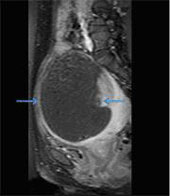

Ablation of the fibroid was carried out using High Intensity Focussed Ultrasound under MRI guidance. The entire procedure lasted about 2½ hours, after which intravenous gadolinium based contrast was administered, and a non-perfused volume of 85-90% was obtained (Fig. 2). The patient tolerated the procedure well.

Fig. 2 - Post Contrast Fat Saturated T1 weighted sagittal image showing a large internal area of non-perfusion (arrows), which is the ablated area